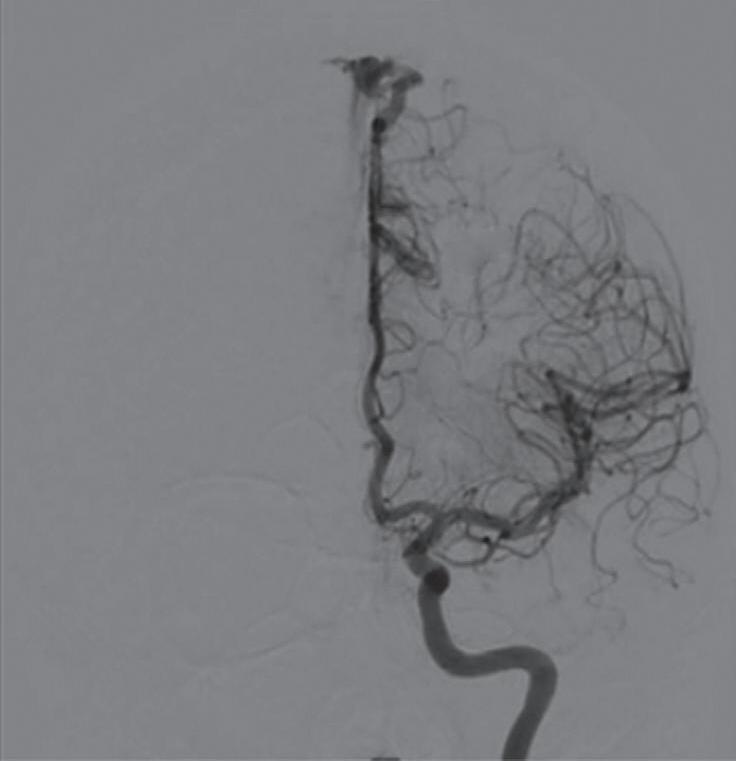

Com relação ao fluxo no interior do nidus, alguns autores classificam-nas em alto fluxo (Fig. 1-8) e baixo fluxo (Fig. 1-9). São consideradas de alto fluxo aquelas em que a opacificação após injeção de contraste ocorre apenas na malformação, em contrapartida, nas de baixo fluxo, ocorre opacificação da MAV e de outras artérias normais do mesmo território vascular. Exemplificando as lesões de alto fluxo temos as malformações arteriais, as malformações arteriovenosas e as fístulas arteriovenosas, enquanto as lesões de baixo fluxo são representadas pelas malformações venosas, linfáticas e capilares.25

Fig. 1-9. RNM T2 em cortes (a) axial e (b) sagital. (c,d) Tractografia axial – sagital, demonstrando a posição de uma MAV não rota localizada na superfície basal do lobo frontal, nos giros orbitários e reto à direita (setas longas). Arteriografia digital cerebral com injeção de contraste via carótida direita, (e) AP e (f) em perfil demonstrando MAV nutrida por ramos da artéria cerebral média e cerebral anterior direita e drenagem para o seio sagital superior (seta curta).